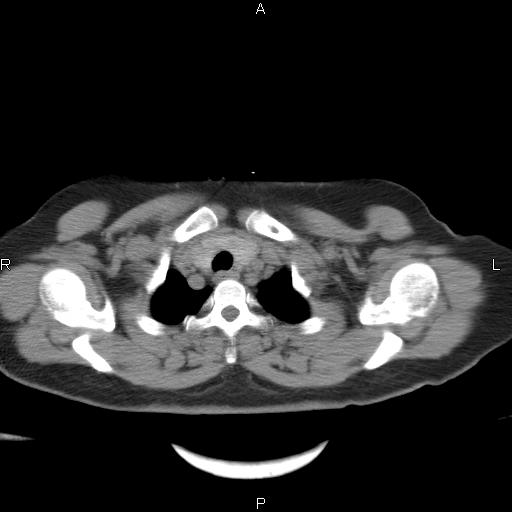

胸腺瘤

女、63Y 双眼睑下垂,早轻晚重。 胸腺瘤???

结果胸腺瘤